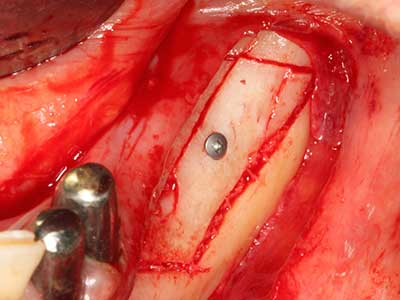

Si es preciso realizar intervenciones quirúrgicas en las que el hueso está en contacto directo con estructuras sensibles, como son los vasos sanguíneos o los nervios, los instrumentos rotativos presentan un enorme potencial de provocar lesiones iatrogénicas. Así, precisamente en la representación de nervios después de una lesión iatrogénica, o en el transcurso de la lateralización de un nervio para resecciones, reconstrucciones o incorporación de implantes, los equipos piezoeléctricos pueden resultar muy útiles para preparar la tapa ósea y retirar las partes de tejido duro cercanas al nervio (fig. 17-20). Por lo general, un ligero contacto del cordón nervioso con el inserto piezoeléctrico no tiene consecuencia alguna; ahora bien, un procedimiento poco cuidadoso con movimientos tipo sierra o piezas de trabajo sobre la base ósea aún existente puede provocar lesiones nerviosas temporales o incluso permanentes. Con todo, el riesgo de sufrir una lesión de este tipo se considera significativamente inferior que en los casos en los que se utilizan sierras y fresas (Pereira, Gealh et al. 2014).

En la cirugía del seno maxilar surgen otros campos de aplicación: En este punto, tras la preparación concéntrica de una tapa ósea de la pared del seno maxilar (que suele tener forma trapezoidal), es posible eliminar patologías y cuerpos extraños del seno maxilar. La tapa ósea se repone después de finalizar la parte intra-antral de la operación y se asegura frente a una posible dislocación mediante cuñas o suturas adaptables.